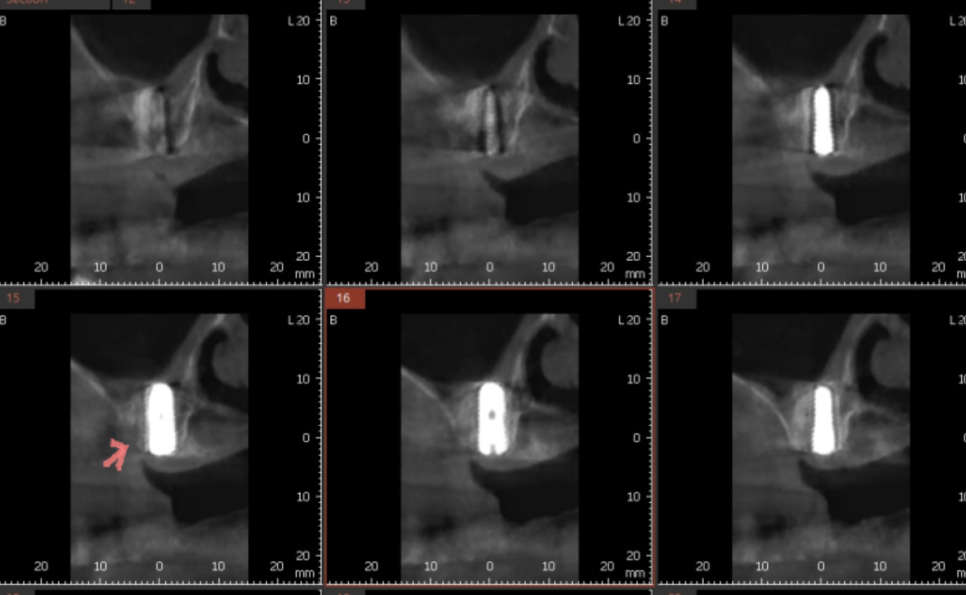

230607

입에서 냄새가 나는 이유는 많지만

신경치료 한 치아 뿌리 끝 부분으로 뼈가 녹아있고

염증 소견이 확인됩니다.

총 4군데에서 문제가 있었지만

가장 안좋은 부분은 오른쪽 위아래

이 부분들은 흔들리고 있었습니다.

230630 녹은 경계를 확인해주세요!

x-ray 상에서도 뼈가 녹은 부분과

녹지 않은 부분이 경계져 보이는 것이 관찰되실겁니다.

녹은 부분은 까맣게 되어있고

괜찮은 부분은 하얗게 말이죠.